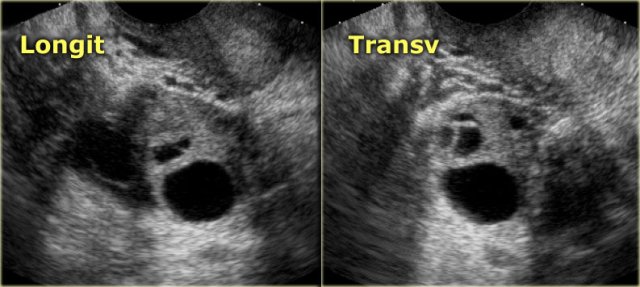

The next case is a unilocular, mildly hypoechoic ovarian lesion with through transmission.

There is no internal or wall vascularity on Doppler.

On ultrasound this can again either be a hemorrhagic cyst or an endometrioma.

Continue with the MR images